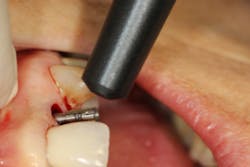

The technical application of this instrument is extremely simple and expedient. New designs have also made RFA instruments easier to use. Older RFA instruments (Ostell) have a cord that connects to the digital readout, many toggle buttons, and a single-use-only peg that inserts into the implant. Newer instruments (PenguinRFA) use a cordless instrument and a multiuse peg that can be sterilized. The button is turned on and the instrument is held close to the peg. Within seconds, you have an ISQ reading (figures 3a and 3b).